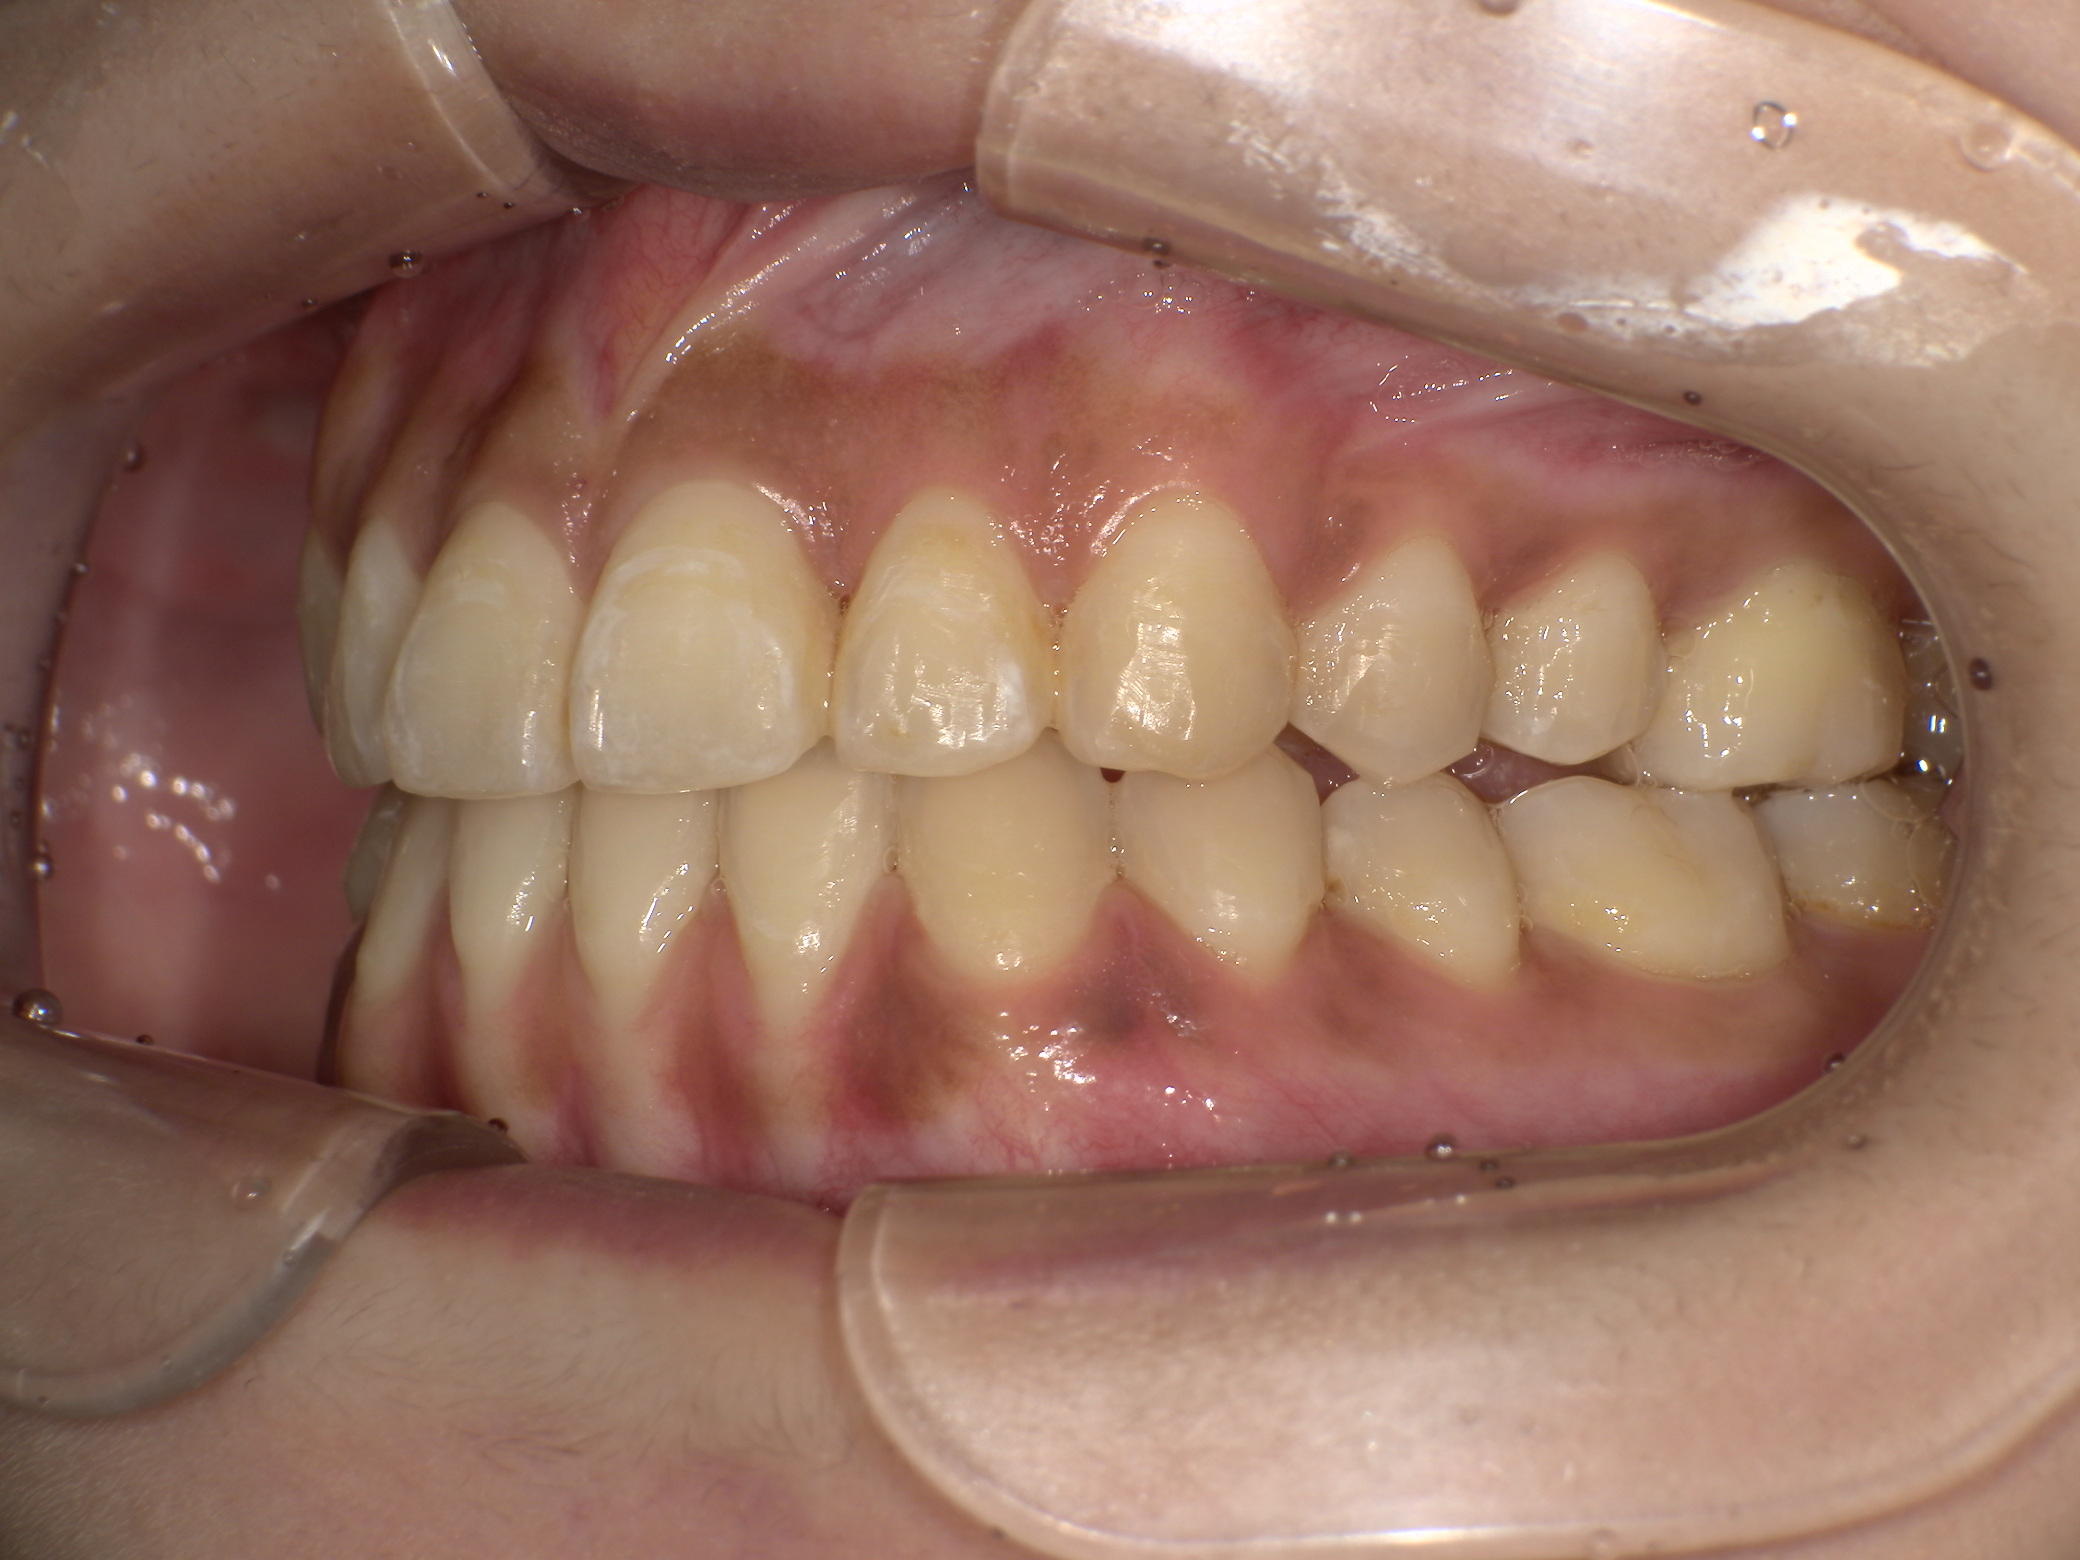

【矯正後】

【治療後】前歯で噛めるようになり、全体的に咬み合わせも良くなったのでとても満足との言葉をご本人より頂きました。

元々下顎前歯1歯欠損のため正中は揃いませんでしたが機能的にはもちろん、見た目も気にならないとのことです